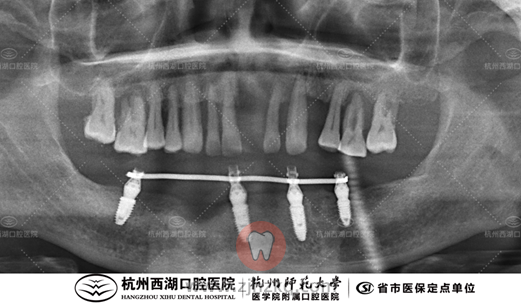

术前CBCT照如下

手术时间:10:00—10:40

种植团队采用All-on-4即刻修复技术,为杨叔叔植入4颗种植体,即日戴牙完成半口修复。